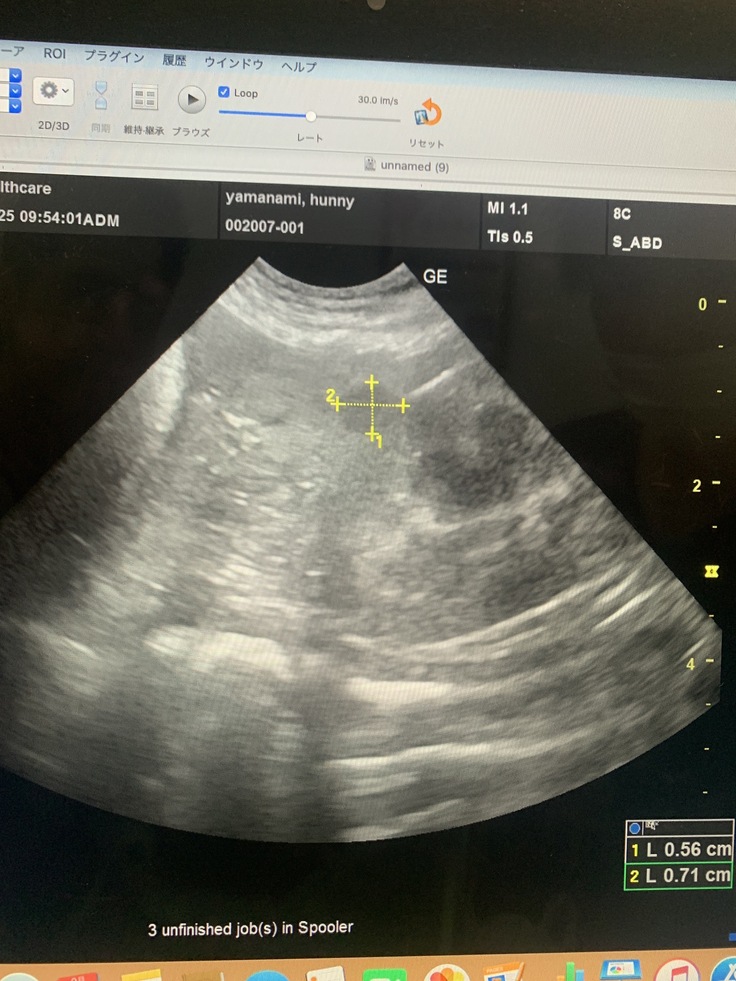

脾臓にしこり、影→1センチ4ヶ所が見つかった